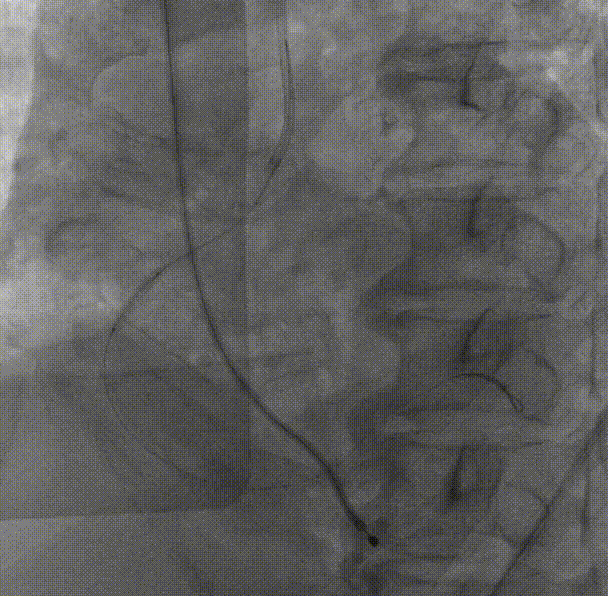

右冠中段开口予Balloon Trek2.5*15mm预扩;于中段至开口依次植入Integrity stent3.5*30mm;Integrity stent3.5*22mm;支架内予Balloon NC Trek3.5*12mm后扩。

回旋支中段予Balloon Trek2.5*15mm预扩,回旋支近中段植入3.0*36mm支架;支架内予Balloon NC Trek3.5*15mm后扩;左主干-前降支近段病变予Balloon Trek2.5*15mm预扩;于左主干-前降支近段植入Integrity Stent3.0*26mm;前降支支架内予Balloon NC Trek3.5*12mm后扩,回旋支开口无受压,远端血流TIMI3级。

复查冠脉造影结果满意。